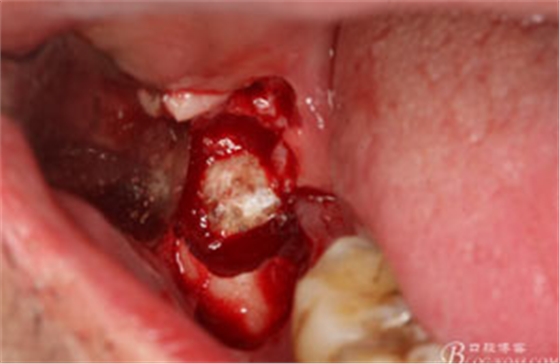

圖7.高速牙鉆去骨。逐漸可見48的牙冠

圖8.刮除牙冠表面的肉芽組織后,可見48 的牙冠